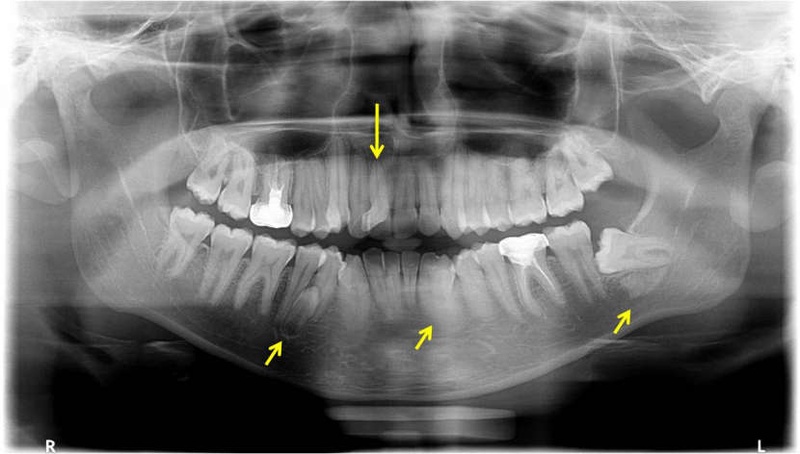

- Răng thừa mọc ngầm: Răng bị kẹt hoàn toàn hoặc một phần trong xương hàm, không mọc lên khỏi nướu.

Vì rất nhiều răng thừa không thể nhìn thấy bằng mắt thường, các phương pháp chẩn đoán hình ảnh là công cụ bắt buộc và quan trọng nhất để xác định:

Chụp X-quang 2D: Sử dụng phim toàn cảnh (Panorama) hoặc Cận chóp. Phương pháp này giúp phát hiện sự tồn tại của răng thừa, đặc biệt là các răng mọc ngầm trong xương hàm.

Chụp CT Cone Beam: Đây là “tiêu chuẩn vàng” cho các ca phức tạp. Phim 3D giúp bác sĩ thấy rõ vị trí răng thừa theo cả 3 chiều, mối liên hệ của nó với chân răng bên cạnh và dây thần kinh, từ đó lên kế hoạch điều trị an toàn nhất.